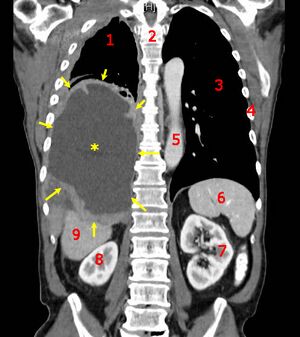

| CT scan showing a left sided mesothelioma with an enlarged mediastinal lymph node | |

More than 80% of mesothelioma cases are caused by exposure to asbestos.[3] The greater the exposure, the greater the risk.[3] As of 2013, about 125 million people worldwide have been exposed to asbestos at work.[13] High rates of disease occur in people who mine asbestos, produce products from asbestos, work with asbestos products, live with asbestos workers, or work in buildings containing asbestos.[3] Asbestos exposure and the onset of cancer are generally separated by about 40 years.[3] Washing the clothing of someone who worked with asbestos also increases the risk.[13] Other risk factors include genetics and infection with the simian virus 40.[3] The diagnosis may be suspected based on chest X-ray and CT scan findings, and is confirmed by either examining fluid produced by the cancer or by a tissue biopsy of the cancer.[2]